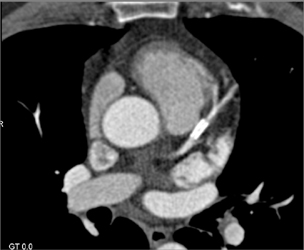

CASE NUMBER 630

Patent LAD Stent